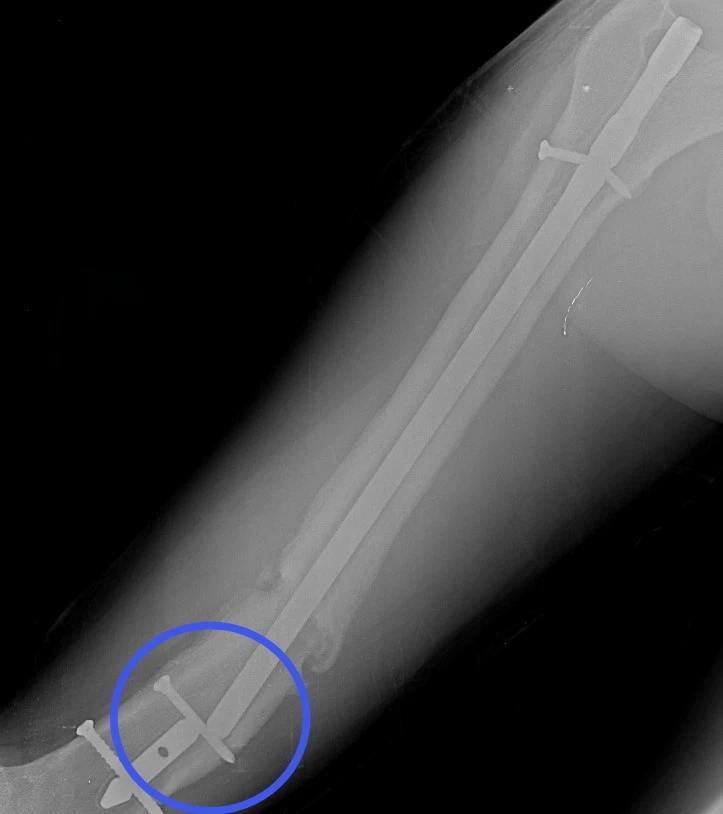

17‑летний Николай поступил к нам с осложнением после операции по поводу перелома бедра. Ранее ему был установлен интрамедуллярный штифт – для фиксации отломков кости с возможностью ранней нагрузки на конечность. Но прежде, чем перелом консолидировался, штифт сломался.

Врачам нужно было найти новое, более подходящее решение, при этом избежать травматичного открытого доступа и обойтись без больших разрезов. Задачу усложнял сломанный внутри кости штифт. Специального серийного устройства для его удаления малоинвазивным способом не существует. Чтобы пройти 40 сантиметров по костномозговому каналу, захватить и извлечь фиксатор, наши специалисты создали свою систему на базе имеющего набора проводников и экстракторов. Тщательное предоперационное планирование принесло желаемый результат в ходе вмешательства.

После успешного удаления прежней конструкции пациенту установили новую надежную систему - с учётом предыдущего опыта. Для этого понадобилось несколько небольших разрезов (не более 2 см). На второй день после операции Николай передвигался по отделению с помощью костылей, уже нагружая оперированную конечность. Сейчас он внимательнее прислушивается к рекомендациям, от выполнения которых зависит благополучие восстановительного периода.